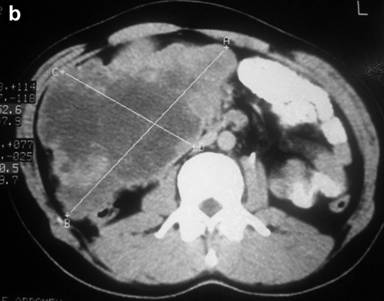

A thirty-year-old man presented with the chief complaint of mass in the right upper abdomen since one and half year. It was gradually increasing in size and was associated with occasional upper abdominal pain. Pain was dull in nature, non-radiating with no specific aggravating and relieving factor. There was history of incomplete bowel evacuation sensation and increased frequency of defecation. There was no history of vomiting, gastrointestinal bleed, jaundice, anorexia and weight loss. On physical examination, there was no pallor, jaundice and lymphadenopathy. A large firm mass about 15x10 cm extending into epigastrium, umbilical and right hypochondrium on per abdomen examination. It had round shape, bosselated surface, smooth margins, and was mobile in the transverse direction. There was no abnormality on digital rectal examination and proctoscopy. Routine laboratory tests were within normal limits. Ultrasound abdomen showed 15x10 cm heterogeneous mass in the umbilical region displacing the adjoining gut loops with no invasion. CECT abdomen showed 15x10 cm size, well defined mass with heterogeneous density in the retroperitoneum extending from pancreas to pelvic brim. It had enhancing peripheral component and non-enhancing (necrotic) central component (Figure 1). Fine needle aspiration cytology of mass smear showed blood only. On exploratory laparotomy there was large hyper vascular mass protruding through the transverse colon mesentery. Mass appeared to be originating from the anterior surface of head of pancreas. It was attached to the whole length of anterior surface of pancreas and macroscopically was not attached with the duodenum except for about one or two cm near the lower end of second part of duodenum (Figure 2). There was no metastasis in liver or peritoneum. Pancreaticoduodenectomy was done. Histopathology showed spindle cell tumor with palisading pattern and foci of necrosis (Figure 3). The mitotic count was up to 15/50 HPF. Tumor was involving duodenal muscularis propria with no infiltration in the duodenal epithelial layer and the pancreas (Figure 4). Immunohistochemical study revealed positive staining for CD117, CD34, vimentin, smooth muscle actin, and negative staining for desmin and CD31 (Figure 5). Based on these findings, the tumor was finally diagnosed as gastrointestinal stromal tumor (GIST) arising from the duodenal wall, growing exophytically and attached with the pancreas without infiltrating the pancreas. Post-operatively patient had biliary leak which was managed conservatively and discharged in satisfactory condition with the advice to take imatinib 400 mg daily.

Figure 2. Macroscopic appearance of resected specimens showing tumor attached mainly along the pancreatic head and with duodenum only near the lower end of second part of duodenum. |